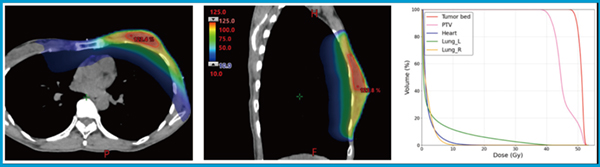

・ガントリ回転角:arc1 179°→270°,arc2 270°→179°

このpartial arcs の活用により,VMATの利点を生かしながら,心臓・肺への不要な線量を効果的に抑制できる2)。さらに,体表近傍の線量分布のロバスト性を確保するため,virtual bolusを用いたスキンフラッシュを実施している3),4)。図1に,SIB-VMATプランの線量分布図とdose volume histogram(DVH)を示す。

図1 左側乳がんに対する SIB-VMAT プランの線量分布図とDVH

partial arcsにより心臓・肺への線量を抑制しつつ,全乳房と腫瘍床への良好な線量分布が得られている。